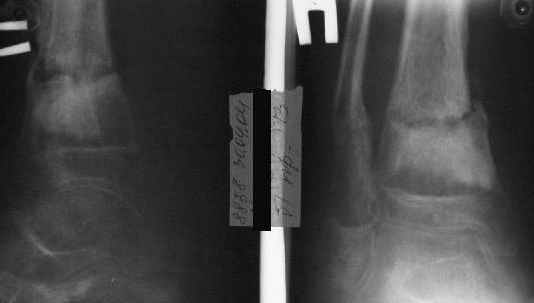

Так как речь зашла непосредственно о травме, см этапные

снимки. Как все было

Первичные

Вытяжение

Фиксация

в гипсе

Промежуточный